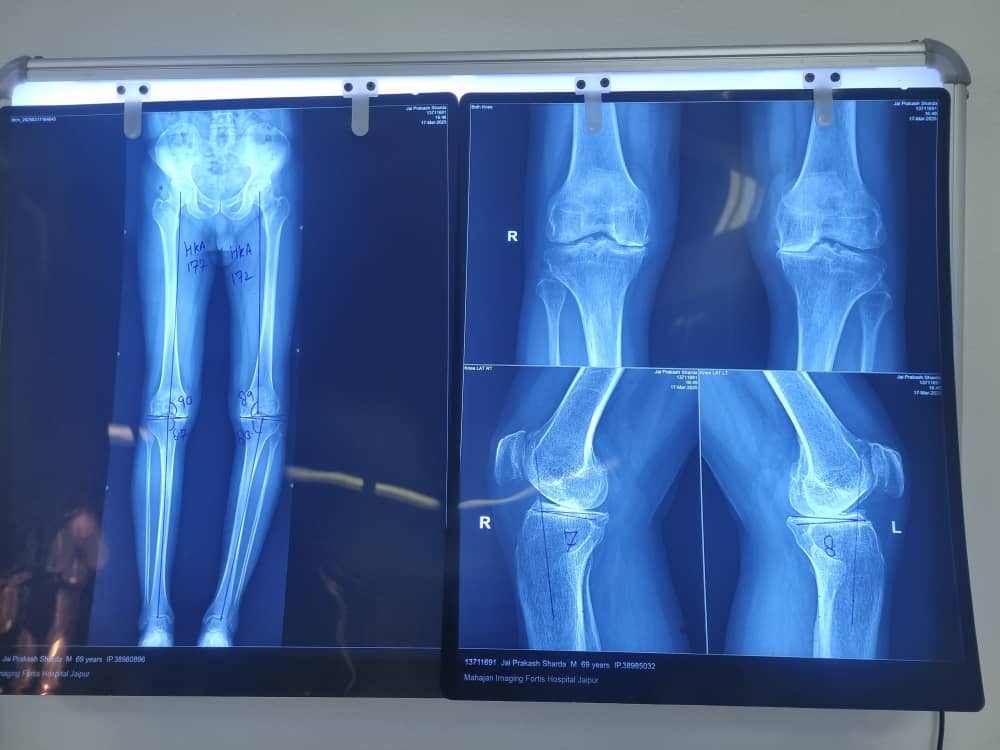

Knee pain can also originate from unexplained synovitis, focal cartilage injury, irritation of nerve root and malalignment of joint line. Dr Raj uses specialised injection techniques to assist you in relieving the joint inflammation, unloading joint compartment and correcting a malaligned joint.

High tibial osteotomy and proximal fibula osteotomies are among the joint preservation surgery techniques that help to unload the arthritic joints, slow down inflammation and help in joint realignment, hopefully negating the need of knee replacement later.